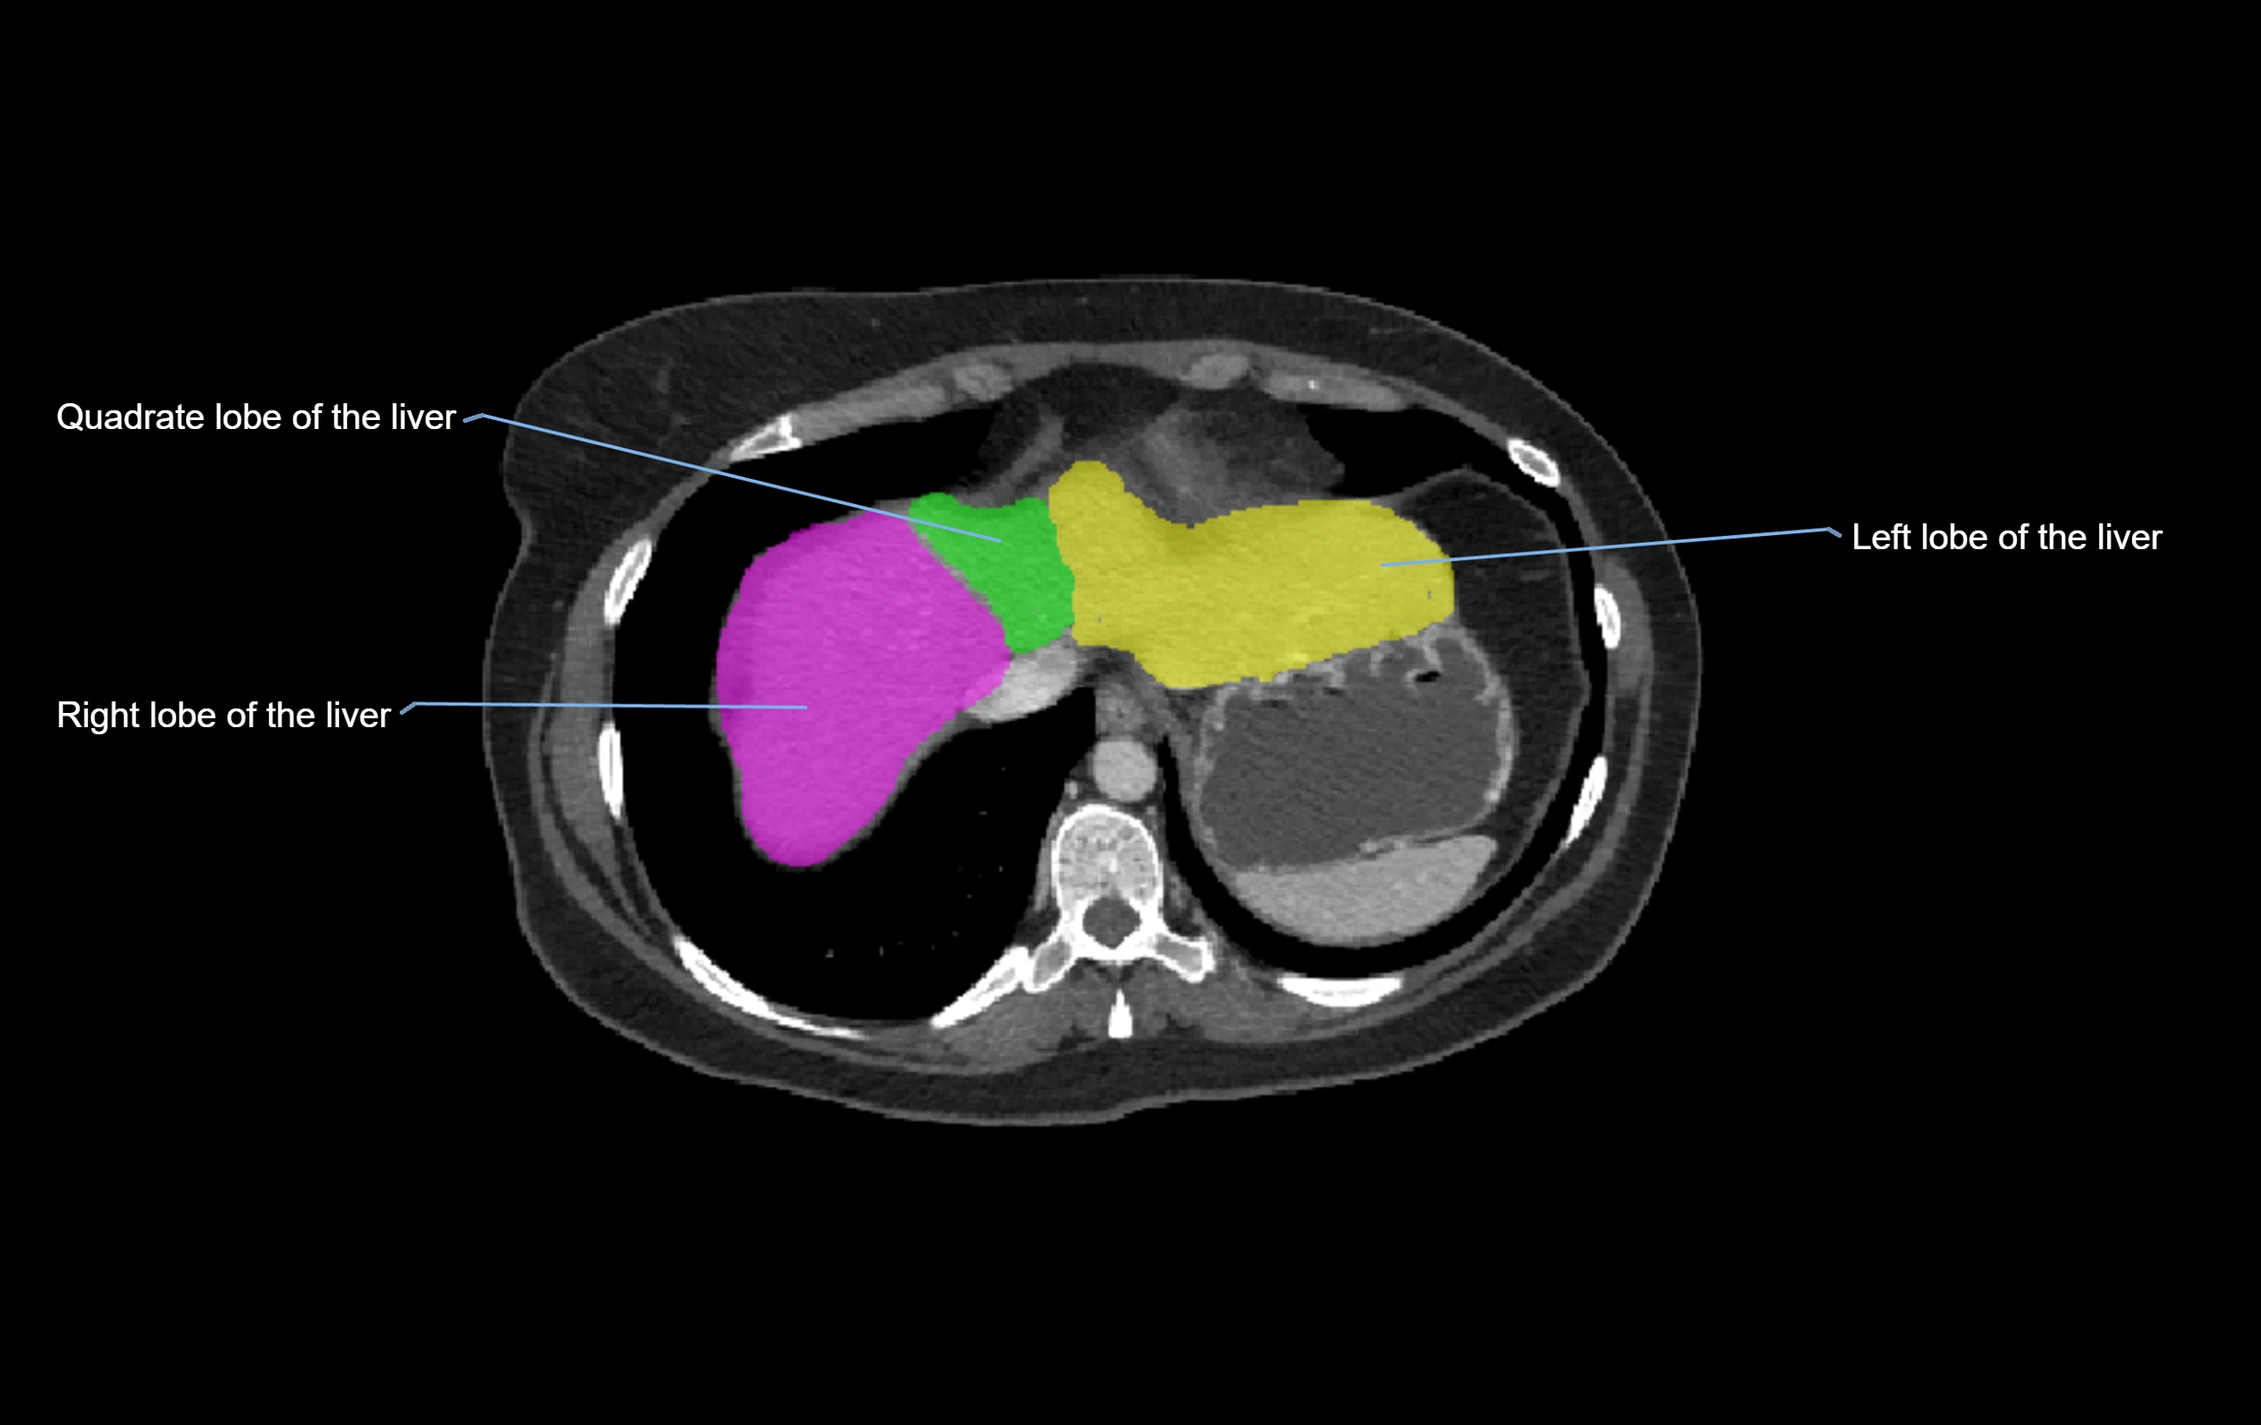

CT Image

image